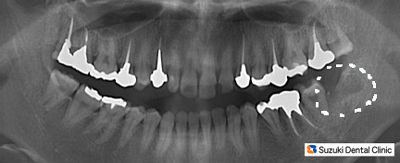

抜歯後のレントゲン

コラム「抜歯後のレントゲン」の画像